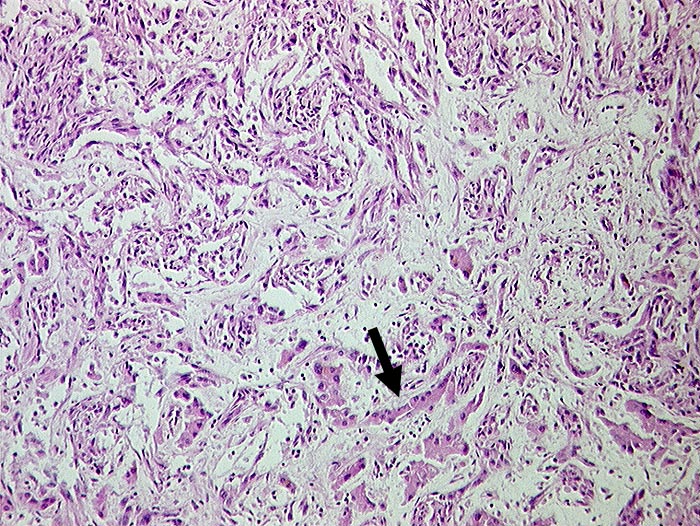

PathoPic ID 687 - Angiosarkom

Angiosarkom

maligner Tumor

Leber

Leber, Gallenwege, Pankreas

Gefässräume ausgekleidet durch atypisches Endothel. Zwischen den neoplastischen Gefässen

►

erhaltene Leberzellbalken.

Histologie